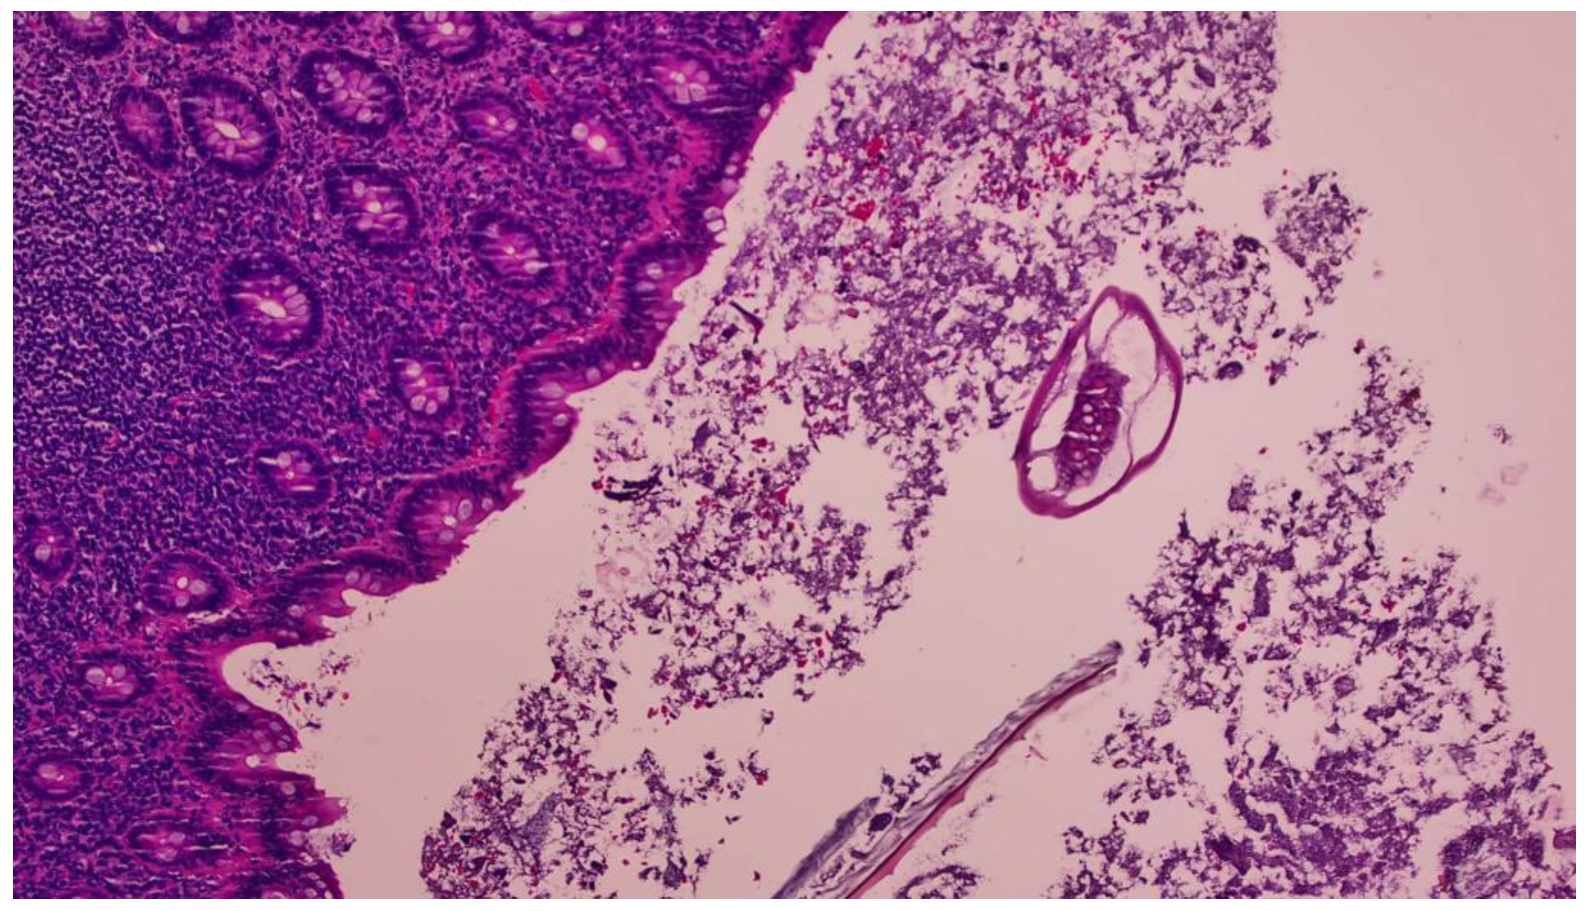

2. Case Report